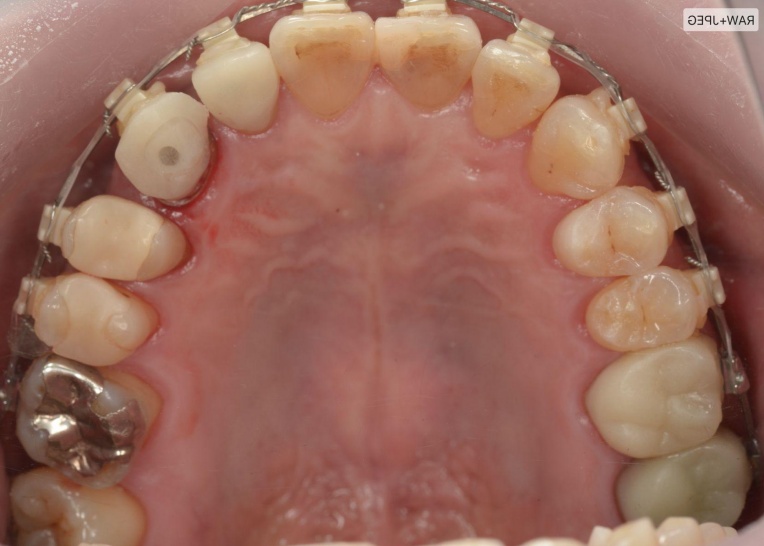

まず、ワイヤー矯正装置を用いた矯正治療を開始します。

折れている歯を一時的に利用しながら、受け口傾向にある噛み合わせが改善するよう、歯の位置を少しずつ調整していきました。

治療前

治療中